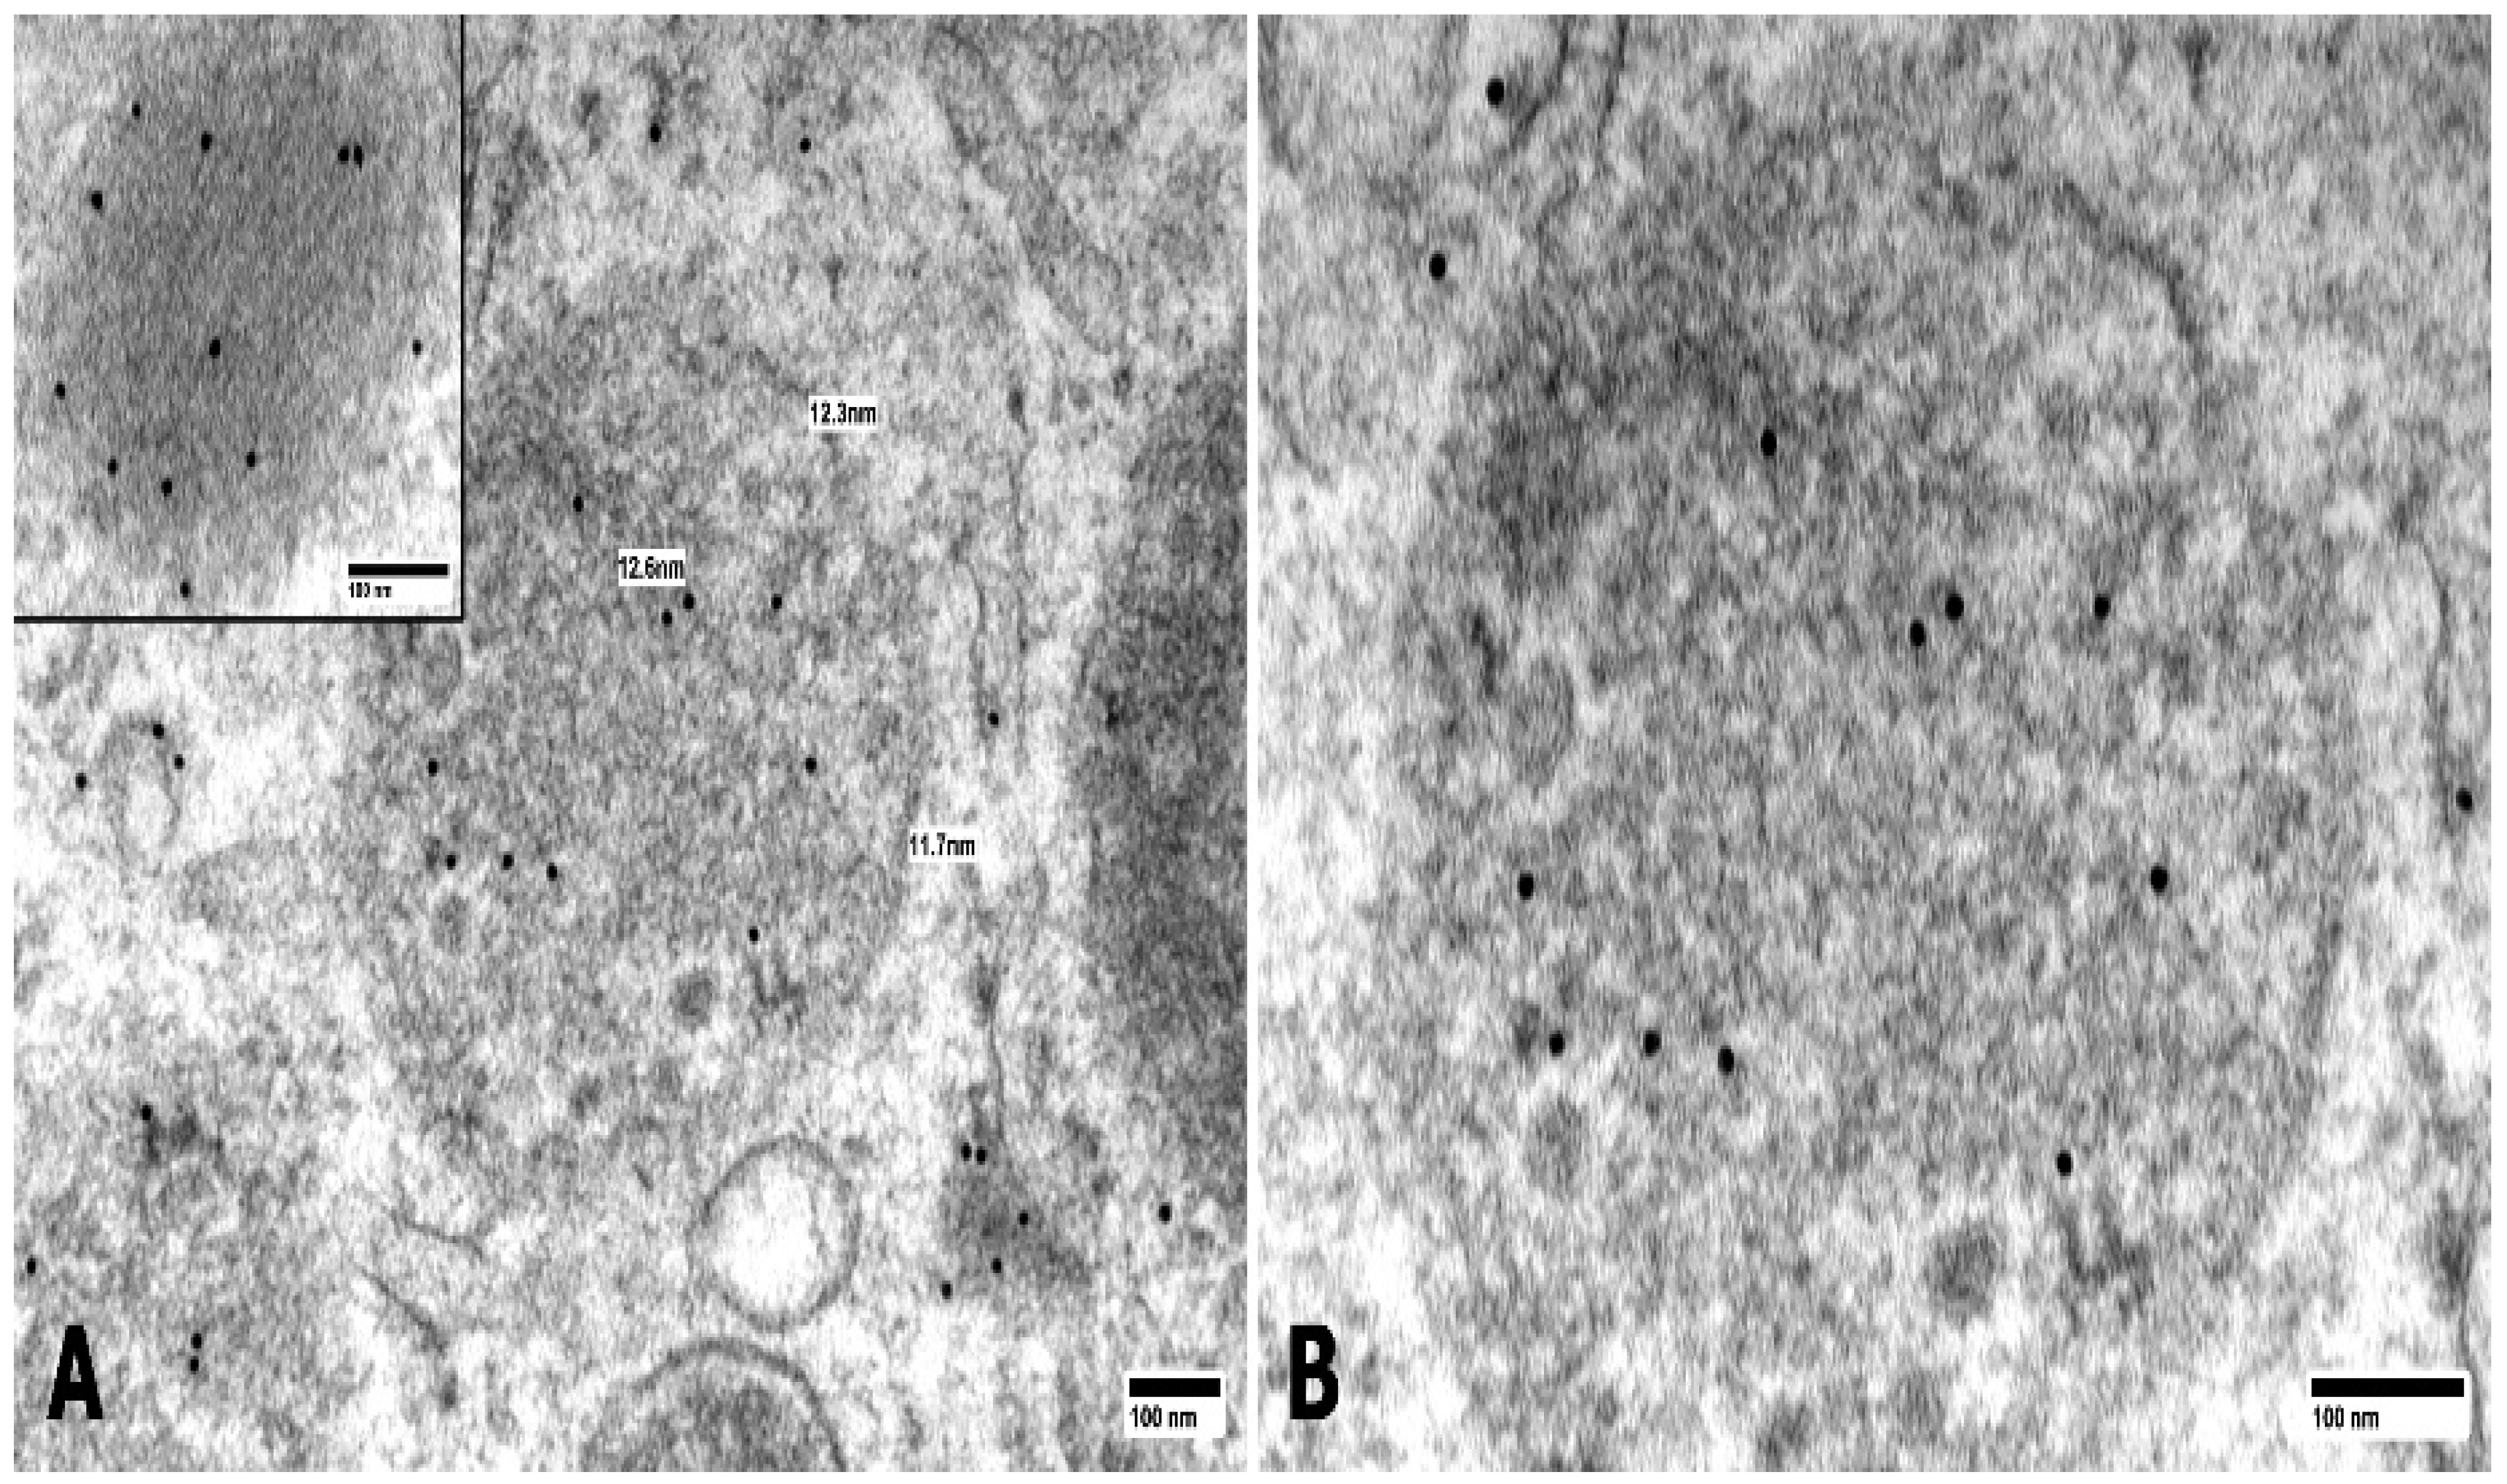

Fibril-Forming Organelles in Mesangial Cells in Renal Biopsies from Patients with Light-Chain-Associated Amyloidosis

3. Results